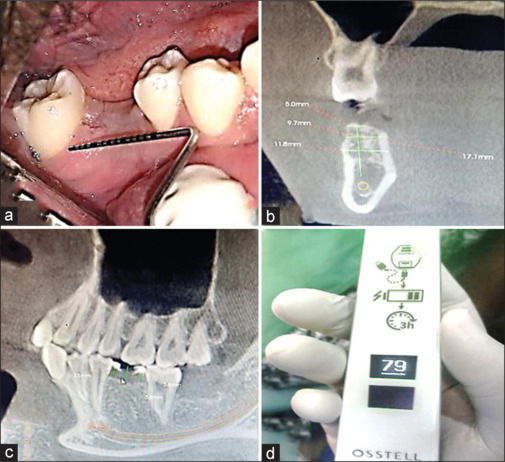

Materials and methods: Fourteen patients were included in this study, of which seven patients were under Group A (delayed) and seven patients were under Group B (immediate). The clinical evaluation was done at baseline, 3 months, and 6 months which includes plaque scores, bleeding on probing, and probing depth. Implant stability was tested by resonance frequency analyzer (implant stability quotient), and radiological evaluation of crestal bone loss was done by cone-beam computed tomography preoperatively and after 6 months.

Results: In this study, there was no statistically significant difference (P > 0.05) in the clinical parameters (plaque index, bleeding on probing, and probing depth) and radiological outcomes within the groups at baseline, 3 months, and 6 months. The implant stability quotient and crestal bone loss between Groups A and B showed a statistically significant difference at baseline and 6 months, wherein there were higher implant stability and decreased crestal bone loss in Group A when compared to Group B.